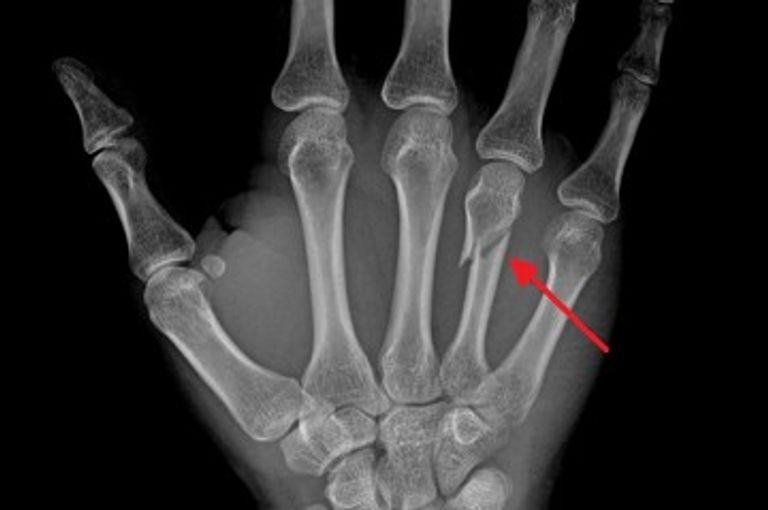

رغم أن الكسور تلتئم بشكل طبيعي، إلا أن العظام لن تتجدد في ظل عدة ظروف، وعندما لا تتجدد العظم، يمكن أن ينتج مشاكل سريرية

على الرغم من أن الكسور تلتئم بشكل طبيعي، إلا أن العظام لن تتجدد في ظل عدة ظروف، وعندما لا يتجدد العظم، يمكن أن ينتج عن ذلك مشاكل سريرية كبيرة، بما في ذلك البتر.